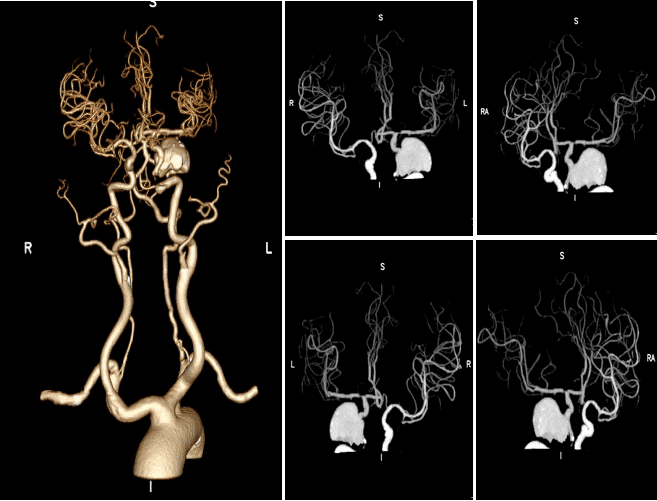

左侧颈内动脉C3段管壁见非钙化斑块,管腔完全闭塞;C5段管壁见钙化斑块,管腔轻度狭窄(0%~29%);C4段动脉瘤,周围见环状钙化,偏右侧见新月形充盈缺损,病灶长径约4.7cm。

左侧颈内动脉C4段动脉瘤形成,其内伴新月形血栓